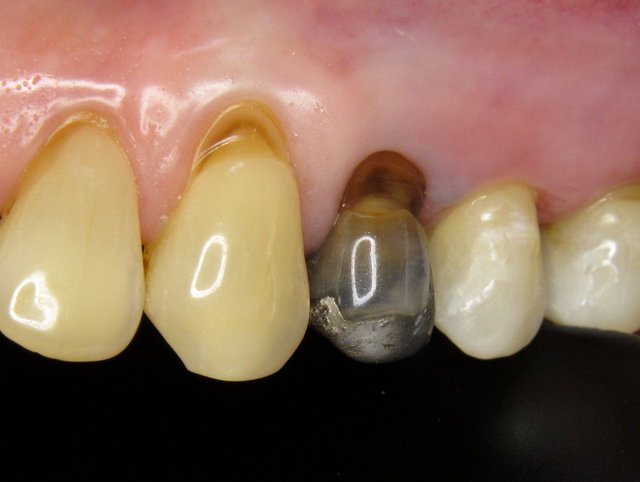

Abfrakturierte natürliche Zahnwand & Putzdefekt ...

Zahnwand-Fraktur neben Amalgam-Füllungen ...